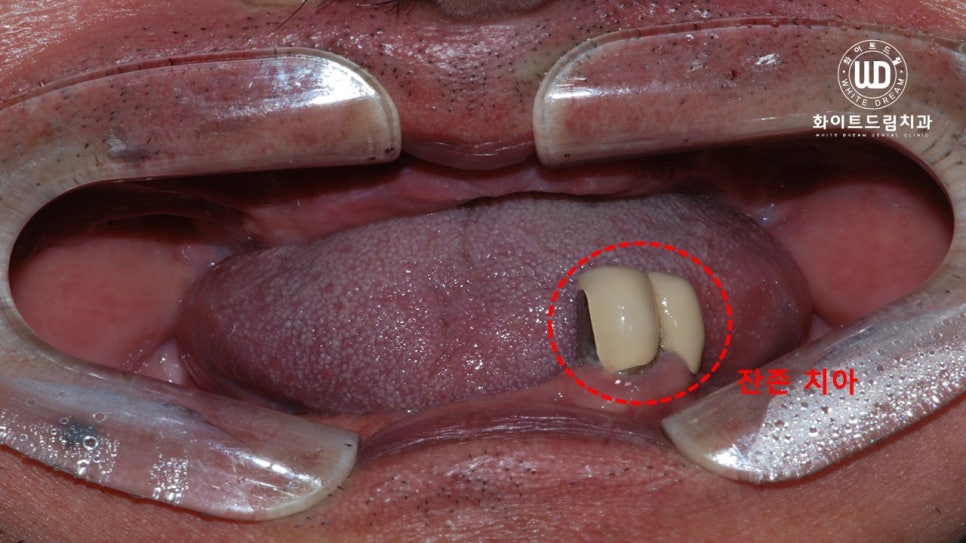

오늘 말씀드릴 환자분은 이전에 틀니를 7~8년 동안 사용했다고 하셨습니다. 틀니를 오랜 기간 동안 사용하셔서 불편하다고 말씀해 주셨는데요. 이러한 이유에 임플란트를 원하시고 저희 치과에 내원해 주셨습니다.

사진상으로 보시면 틀니를 오래 착용하시면서 하악 골소실이 심하고, 잇몸 폭도 현저히 줄어 있는 상태임을 확인할 수 있었습니다.

더욱 자세한 치료를 위해 파노라마 사진을 촬영하여 살펴보았습니다. 하악의 잔존 치아도 제 기능을 하지 못할뿐더러 골소실이 함께 나타나 있었습니다. 그래서 하악 잔존 치아 2개를 발치하여 상하 전체 치조골 이식을 동반한 임플란트 식립을 진행하였습니다.